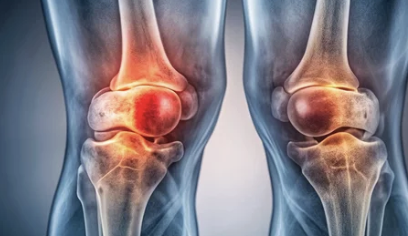

3. 붓기와 열감으로 나타나는 중기 증상

물이 더 차면 겉으로도 변화가 분명해집니다.

중기 증상의 특징

- 무릎이 눈에 띄게 부음

- 손으로 만지면 말랑하거나 팽팽한 느낌

- 열감 동반

- 압통 발생

이 단계에서는

단순 피로 누적이 아니라 염증 반응이 동반된 경우가 많습니다.